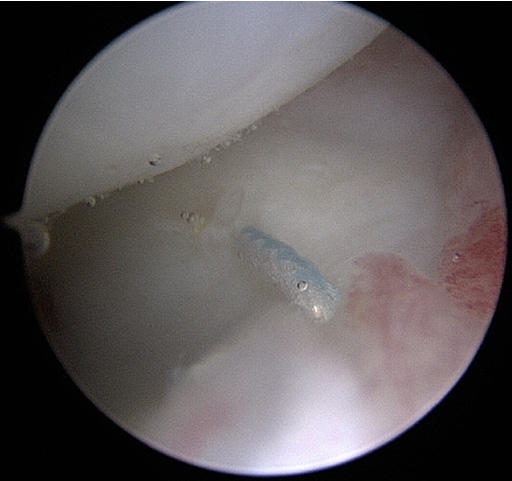

손목 사용이 많은 환자나 보존적 치료에 효과가 없는 경우에는 수술적 치료를 고려할 수 있습니다. 수술 전 MRI나 수술 당시 손상된 부위에 따라 수술방법이 달라지며, 만약 원위요척골 관절의 불안정성이 유발된 경우에는 TFCC의 골봉합 방법이 필요합니다. 전 세계적으로 대략 3가지 방법(관절내시경으로 봉합하는 방법, 전통적인 개방적 방법, 두가지를 혼합한 방법)이 있습니다.

본원에서는 국내에서 선도적으로 두 가지를 혼합한 관절내시경을 이용한 골터널 고정방법을 시행하고 있으며, 많은 환자들에게서 좋은 결과를 보이고 있습니다.